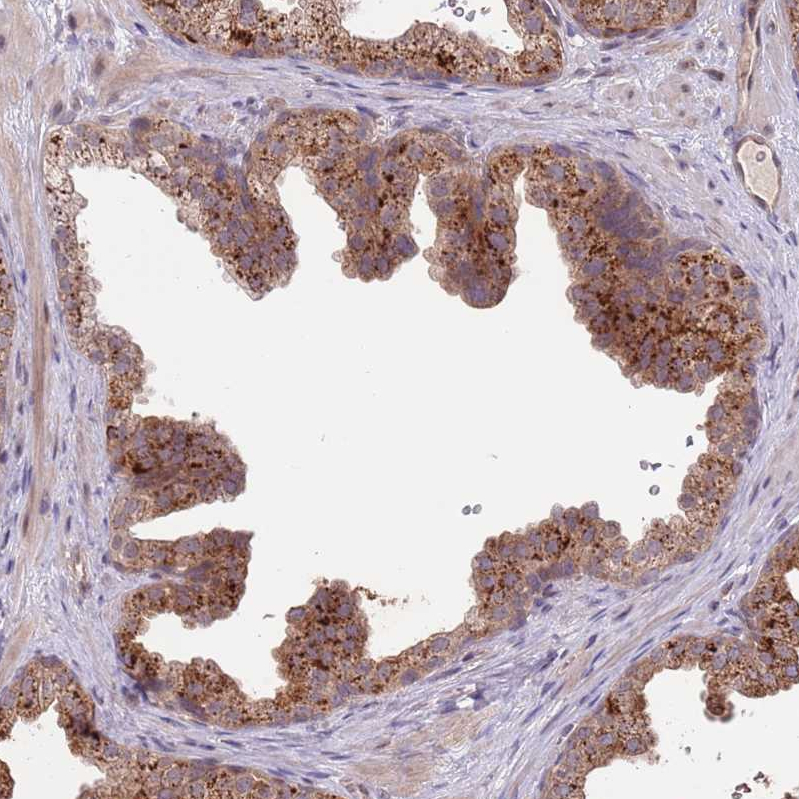

Immunohistochemical staining of human placenta shows moderate cytoplasmic positivity in trophoblastic cells.